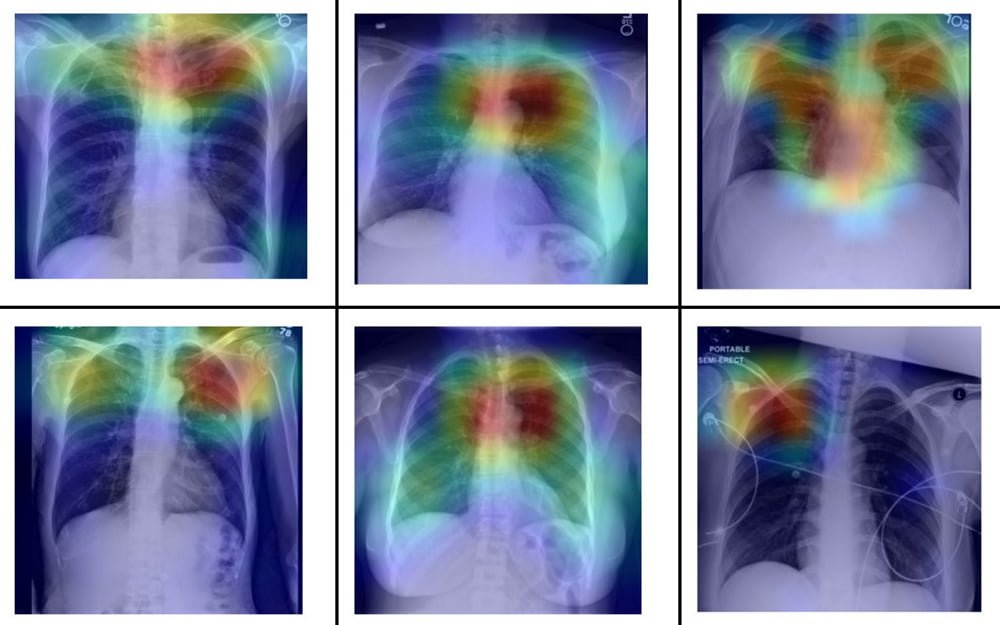

In ihrer systematischen Untersuchung zeigen die Forscher außerdem, dass das Problem deutlich größer als angenommen ist: Standard-KI-Systeme können die Ethnizität aus Röntgen- und CT-Bildern mit hoher Leistung vorhersagen und das sogar aus beschädigten, beschnittenen oder verrauschten Bildern und anhand verschiedener Körperregionen.

Titelbild: Banerjee et al. | Via: Arxiv